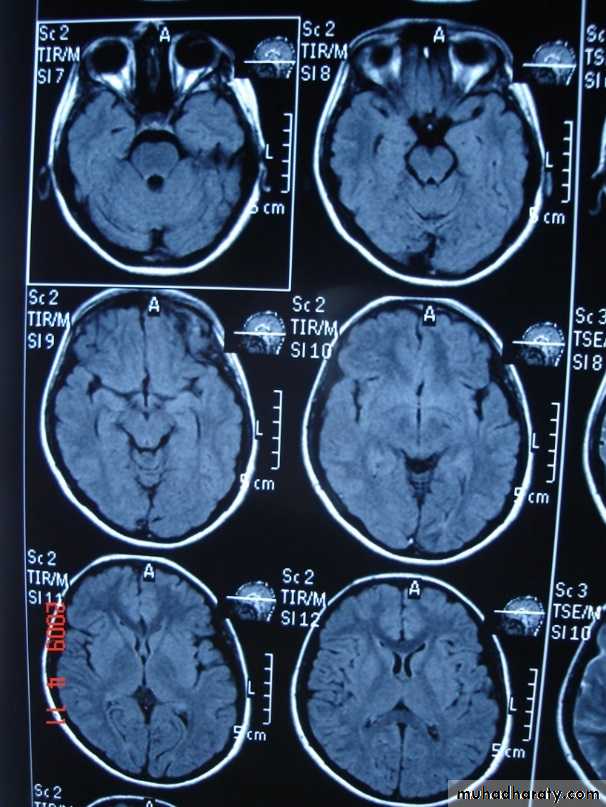

Sagittal fluid-attenuated inversion recovery (FLAIR) weighted image through a brain lesion), showing homogeneity of the lesion, lack of a perceptible wall, lack of internal complexity, and CSF signal intensity. There is associated brain displacement. These imaging features are typical of an arachnoid cyst.